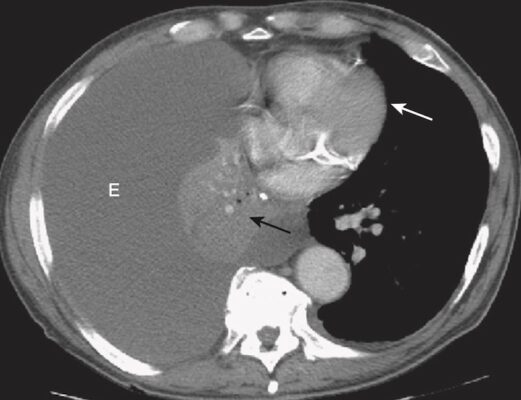

- Ở một bệnh nhân người lớn bị mờ nửa phổi, không có hình ảnh phế quản chứa khí và ít hoặc không có sự dịch chuyển của các cấu trúc lồng ngực di động, cần nghi ngờ một ung thư biểu mô tuyến phế quản gây tắc nghẽn, có lẽ có di căn đến màng phổi. Chụp cắt lớp vi tính (CT) ngực sẽ cho thấy những bất thường này (Hình 5).